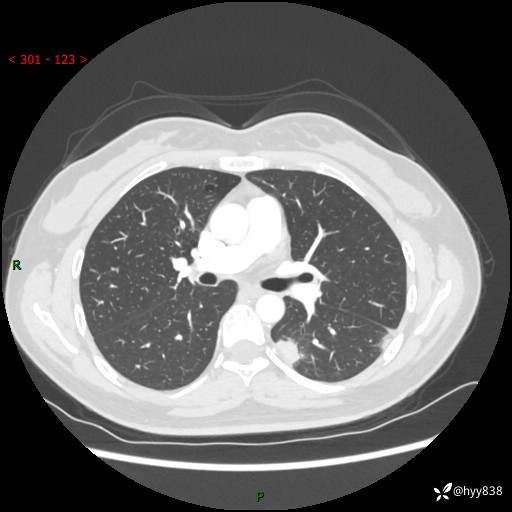

【患者信息】:36岁/女

【主诉】:左侧下胸部阵发性疼痛2周,乏力1周

【现病史及既往史】:患者自诉2周前饮酒后出现左侧下胸部阵发性疼痛,不随呼吸改变,无咳嗽咳痰、头晕头痛、咳血、呼吸困难等不适,于当地第一人民医院查胸部CT提示肺部感染,随后前往我院门诊给予抗感染(左氧氟沙星)治疗1周,自诉胸痛较前好转,感乏力、头晕,偶尔干咳,无咳痰,无发热、畏寒、胸闷、咯血、四肢酸痛、腹泻、腹痛等不适,门诊复查胸部CT提示:左肺下叶感染,病灶较前增加增大,遂以“肺部感染”收入我科。 起病以来,患者精神、饮食、睡眠可,大小便正常,体力体重无明显变化。

【检查】:胸部CT增强(外院平扫)